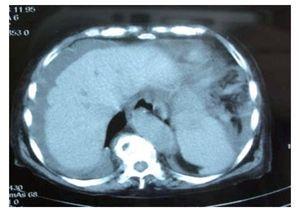

Varón de 35 años con estado de choque y dolor abdominal. La tomografía computarizada de abdomen mostró líquido libre en cavidad peritoneal y una lesión de naturaleza mixta sólidoquística en intestino delgado (Figura 1). La laparotomía confirmó una lesión yeyunal extra-mucosa con componente quístico multilocular (Figuras 2 y 3), asociado a hemoperitoneo. Se realizó resección yeyunal con anastomosis primaria. El estudio histológico mostró una lesión estromal con transformación multiquística, con expresión de c- KIT y CD34.

¿ Figura 1. TAC abdominal que demuestra líquido libre compatible con hemoperitoneo.